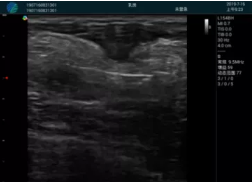

可視化甲狀腺穿刺引導(dǎo)

頸動脈血流充盈飽滿,無外溢

肝內(nèi)血管顯示清晰,血流敏感無外溢

2001年美國健康護(hù)理研究和質(zhì)量監(jiān)督局(AHRQ)批準(zhǔn)了一項(xiàng)關(guān)于提高患者安全性的報(bào)告,建議:在頸內(nèi)靜脈中心置管術(shù)時(shí)使用超聲引導(dǎo)。此后超聲引導(dǎo)穿刺被用于幾乎所有的急診穿刺操作,尤其是血管穿刺。

便攜超聲在急診穿刺中的應(yīng)用:

* 提高了穿刺成功率

* 減少了穿刺損傷及并發(fā)癥

* 縮短了操作時(shí)間

* 減輕了患者痛苦